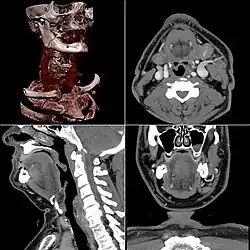

La tomodensitométrie (TDM), dite aussi scanographie, tomographie axiale calculée par ordinateur (TACO), CT-scan (CT : computed tomography), CAT-scan (CAT : computer-assisted tomography), ou simplement scanner ou scanneur pour l'appareil[a], est une technique d'imagerie médicale qui consiste à mesurer l'absorption des rayons X par les tissus puis, par traitement informatique, à numériser et enfin reconstruire des images 2D ou 3D des structures anatomiques. Pour acquérir les données, on emploie la technique d'analyse tomographique ou « par coupes », en soumettant le patient au balayage d'un faisceau de rayons X[1].

Dans les appareils modernes, l'émetteur de rayons X (tube à rayons X) effectue une rotation autour du patient en même temps que les récepteurs situés en face, et qui ont pour fonction de mesurer l'intensité des rayons après qu'ils ont été partiellement absorbés durant leur passage à travers le corps. Les données obtenues sont ensuite traitées par ordinateur, ce qui permet de recomposer des vues en coupes bidimensionnelles puis des vues en trois dimensions des organes. On peut faire ressortir le contraste de certains tissus, en particulier des vaisseaux sanguins, en injectant un produit dit « de contraste » (un complexe de l'iode) qui a la propriété de fortement absorber les rayons X et donc de rendre très visibles les tissus où ce produit est présent (qui apparaissent alors hyperdenses, c'est-à-dire plus « blancs » sur l'image). Grâce aux tomodensitomètres multidétecteurs (ou multi-barrettes) à acquisition spiralée (déplacement lent de la table d'examen durant l'acquisition), on obtient depuis les années 1990 une exploration très précise d'un large volume du corps humain pour un temps d'acquisition de quelques secondes.

Le principe de la tomodensitométrie repose sur le théorème de Radon (1917) qui décrit comment il est possible de reconstruire la géométrie bidimensionnelle d'un objet à partir d'une série de projections mesurées tout autour de celui-ci. Cette méthode peut être étendue à la reconstruction de la tomographie interne d'un objet à partir de la façon dont les rayons le traversant sont absorbés suivant leurs angles de pénétration. Toutefois, les calculs nécessaires à cette technique la rendaient impraticable avant l'avènement des ordinateurs. L'ordinateur attribue à chaque pixel d'image une valeur d'échelle de gris proportionnelle à l'absorption des rayons X par le volume corporel correspondant. La densité mesurée en unités Hounsfield (UH) va de -1000 pour l'air à +1000 pour l'os dense cortical, en passant par -50 pour la graisse et 0 pour l'eau.

Celles-ci se présentent sous la forme de « coupes » ou tranches d'épaisseur millimétrique (de 0,4 mm à 10 mm) que le radiologue peut étudier dans tous les plans de l'espace (sagittal, axial, coronal et obliques), et qu'il s'agit de post-traiter (augmentation de l'épaisseur des coupes visualisées, mise en valeur de certaines densités, reconstructions volumiques en 3D, extraction des vaisseaux ou des structures osseuses, navigation virtuelle endoscopique, etc.).